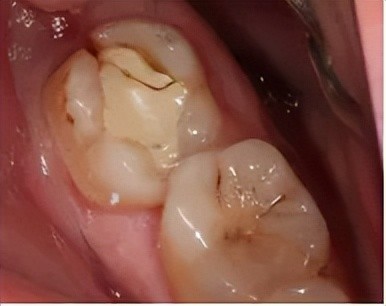

牙隐裂,又称不全牙裂或牙微裂,是指牙齿表面由于承受异常咬合力而产生的非生理性细小裂纹。这种裂纹在早期常不易被发现,但随着裂纹加深,可能会引起牙齿敏感、咀嚼不适、咬合痛或自发痛等症状。牙隐裂是牙齿敏感及牙痛的原因之一。

重度隐裂:裂纹可能累及牙髓,甚至导致牙体折裂,最终可能需要拔牙。

裂纹达牙本质:制备窝洞后充填治疗或采用冠修复。

裂纹累及牙髓:需要根管治疗后进行冠修复保护。

裂纹已达髓底:牙齿无法保留,需拔除后修复。